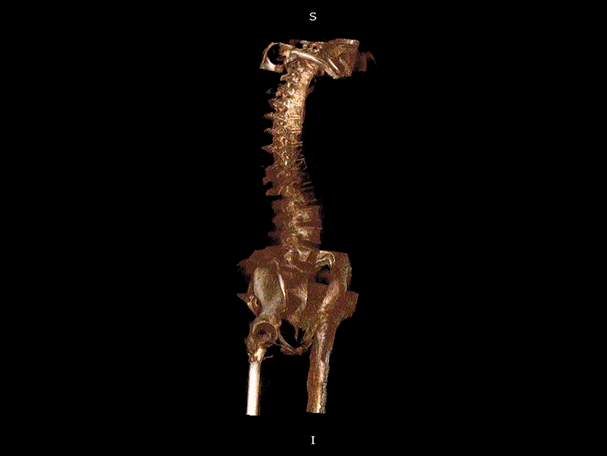

三维脊柱应用

精准诊断

手术方案规划

术后随访

• 脊柱评估

VR体绘制重建